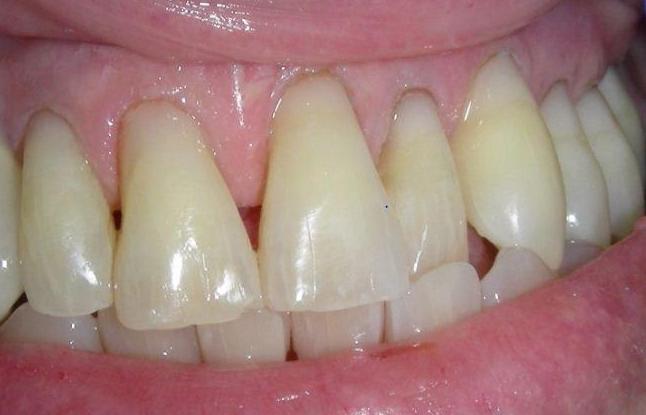

Laminate composite resin veneers

This patient came to our office with severely eroded enamel. This condition can result from excessive use of acidic foods (such as lemons or soda), or other causes.

When the enamel is not present to protect the teeth, the softer dentin underneath is far more vulnerable to further destruction.

This case was restored with composite resin veneers, and was completed in one session. In cases such as this, little or no drilling of the natural tooth structure is necessary.